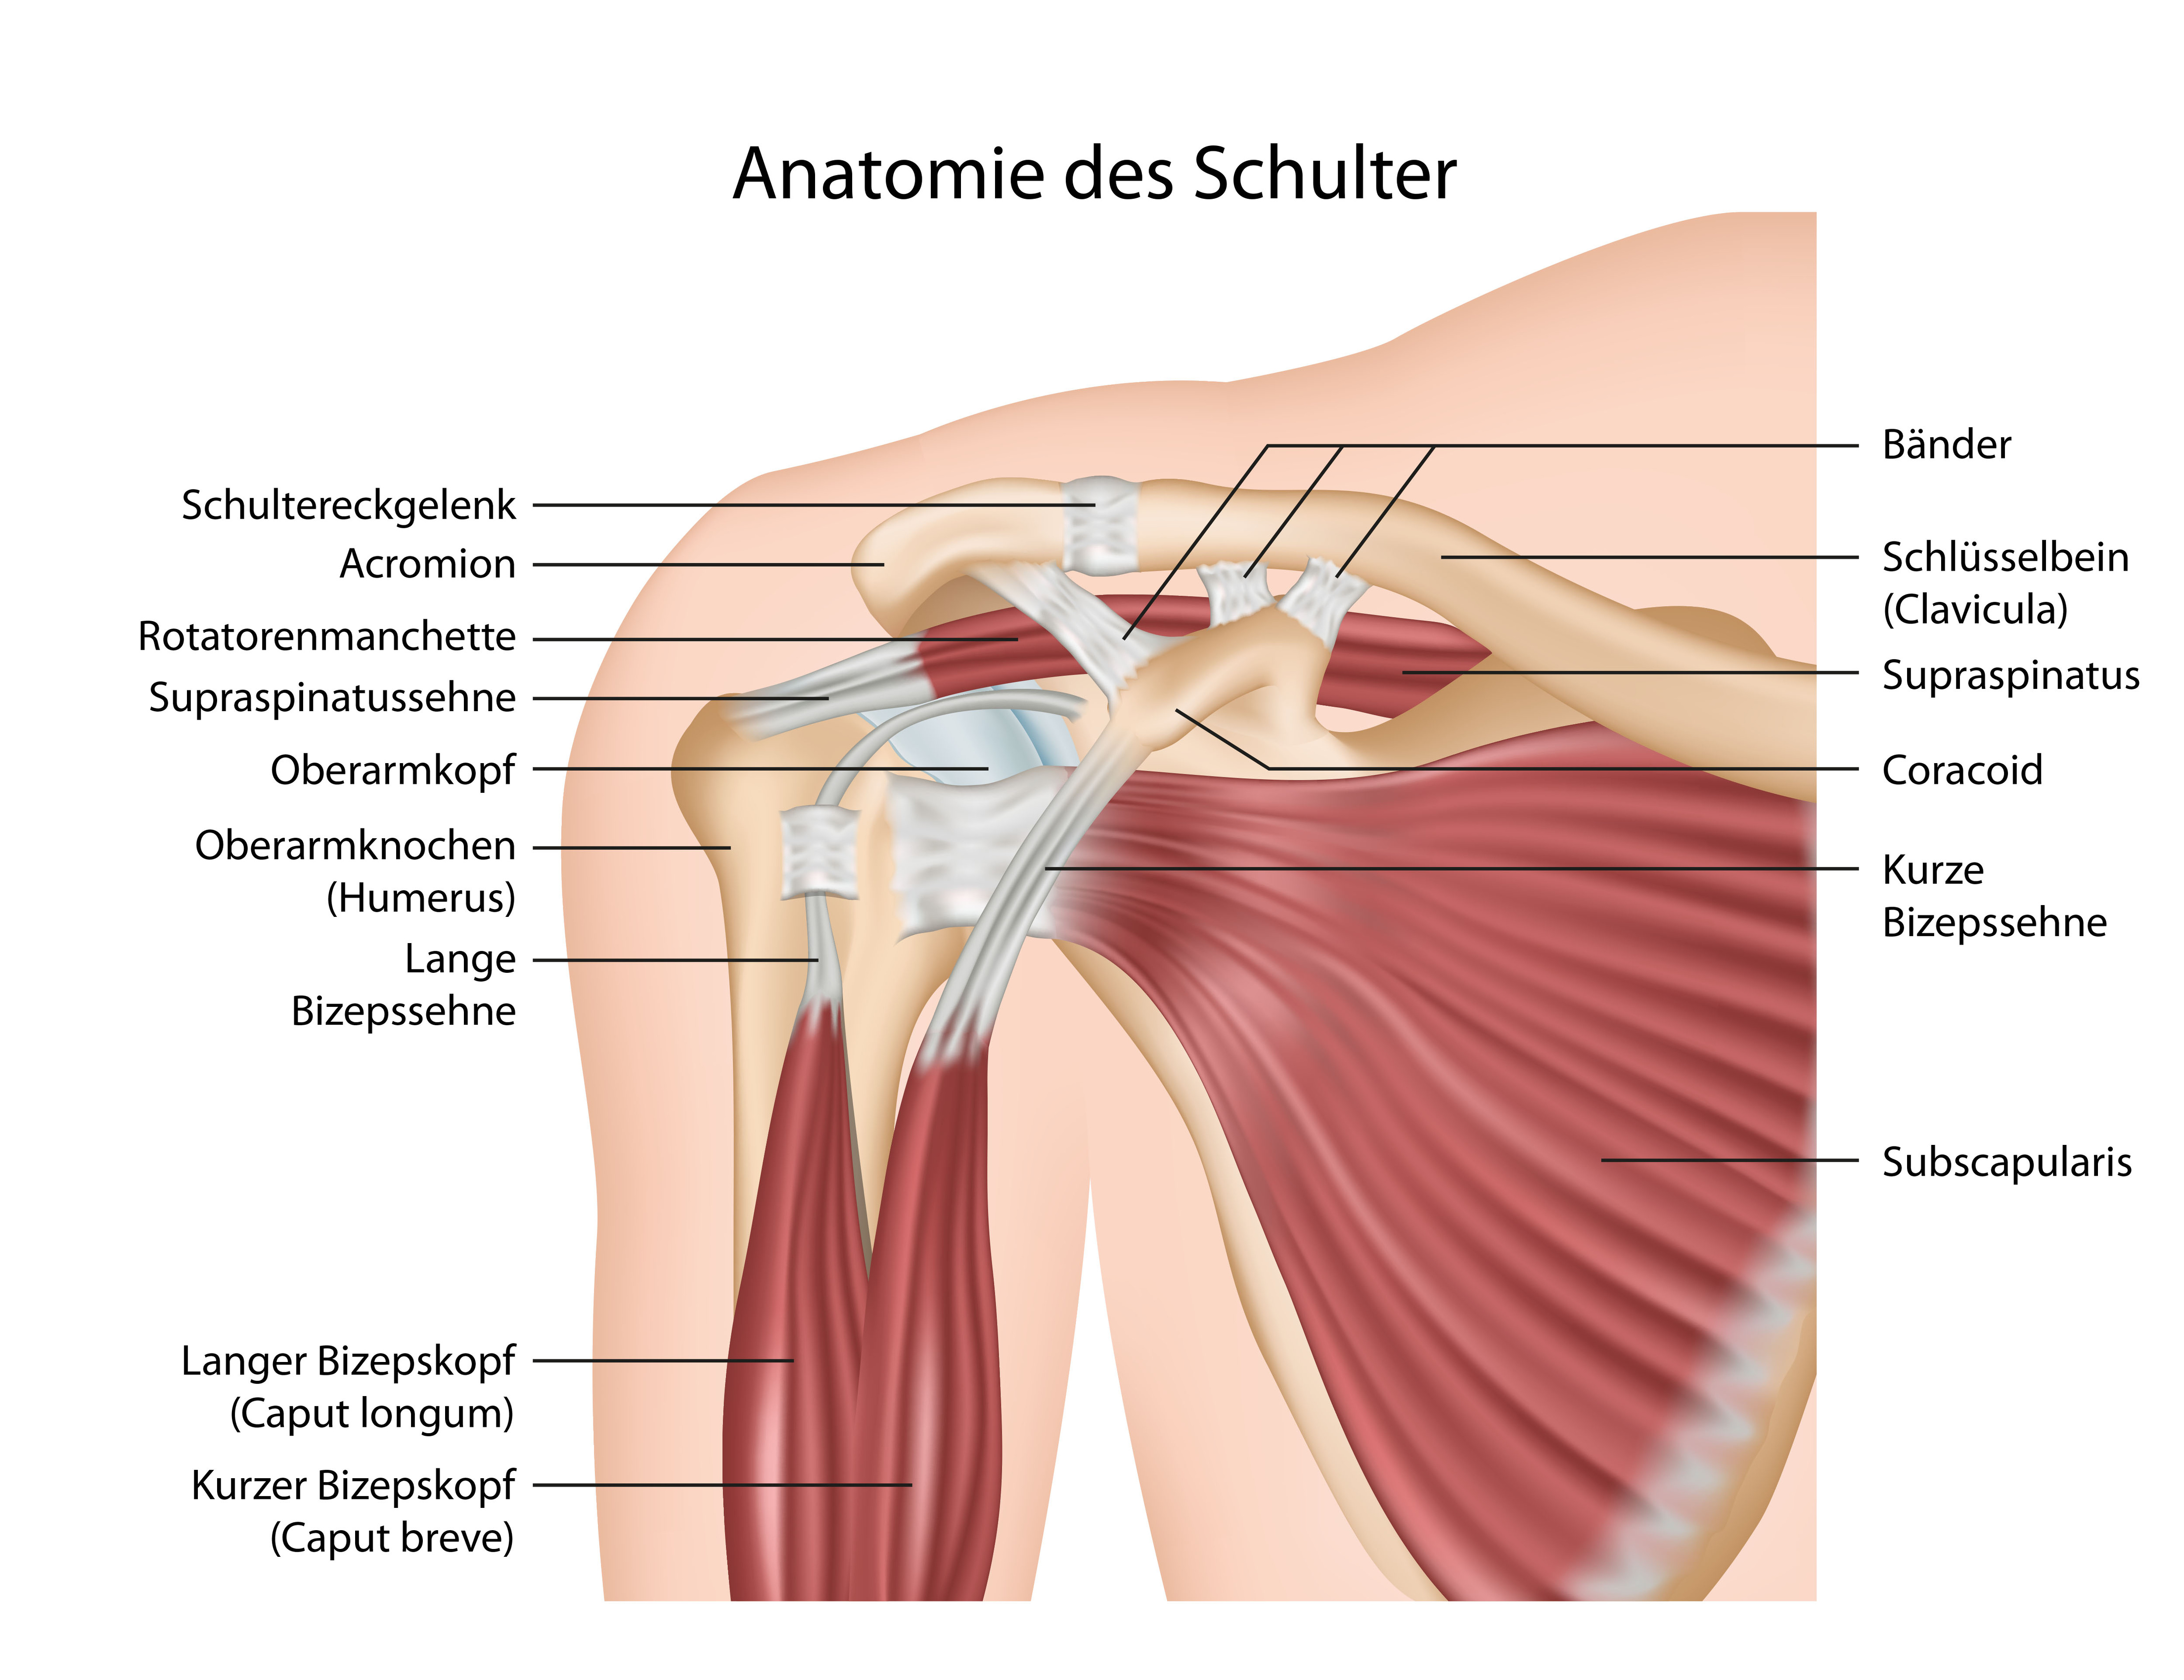

Фотографии мышц ротаторной манжеты плеча